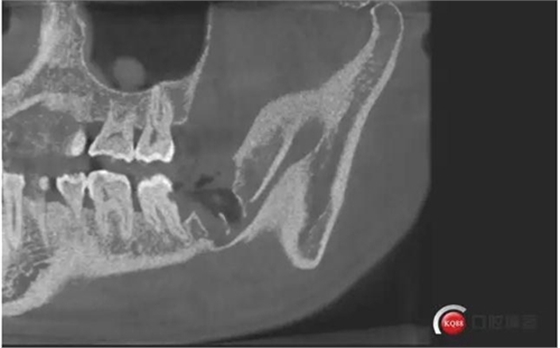

下面拔除后的片子,可以清楚的看到,牙根穿破神經(jīng)管。

拔牙前后對比一下,(拔除前)

1500633362_825152.jpg拔除后。 可以看到神經(jīng)管皮質(zhì)骨的不連續(xù)。